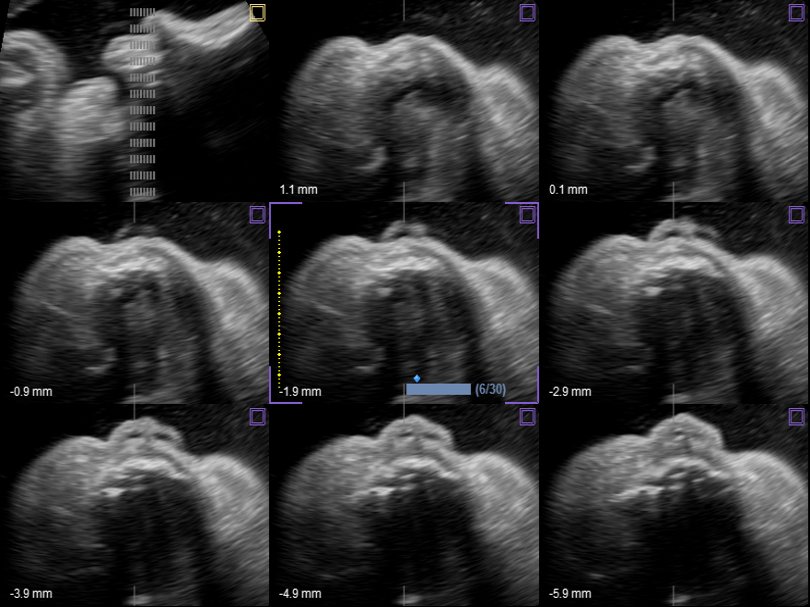

EV3-10T

Endocavity transducer (3-10MHz)

Application:

GYN, OB, Fetal Echo, Urology, EM

EC3-10T

Endocavity transducer (3-10MHz)

Application:

GYN, OB, Fetal Echo, Urology, EM

VE3-10H

High density volume endocavity transducer (3-10MHz)

Application:

GYN, OB, Urology, EM